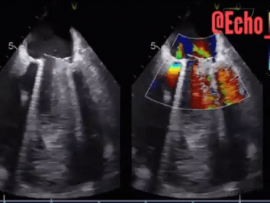

Lee masSevere Mitral Stenosis and Moderate Aortic Regurgitation Mohammed Zidan, MBBCH, M.Sc Cardiology (Cardiology, Echocardiography and interventional Cardilogy Specialist at Al-Azhar university), Cairo, Egypt.